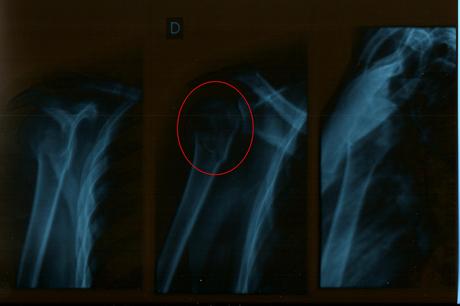

Et voici la cause de ma pause… Une fracture du col de l'humérus droit en mots précis et clairs…